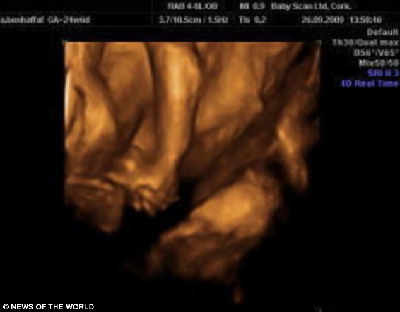

這是連體嬰兒母親懷孕24周的掃描照片,圖中可見(jiàn)胎中嬰兒手牽著手。

據(jù)介紹,兩個(gè)小家伙于去年12月出生在倫敦大學(xué)醫(yī)院。早在安琪懷孕12周的時(shí)候,B超顯示,她懷上一對(duì)連體嬰兒。在24周的時(shí)候,則能從B超照片中看出,兩個(gè)小家伙的手緊緊握在一起,親密無(wú)間的樣子,讓人看了不免動(dòng)容。